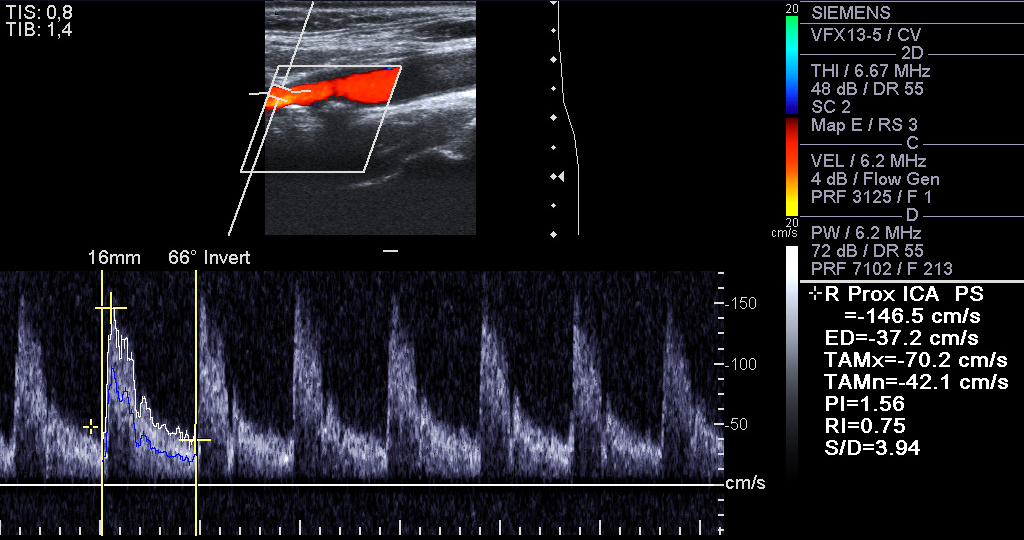

3. 2. 경동맥 죽상경화증

총경동맥은 뇌와 목에 혈액을 공급한다.[25] 경동맥이 심하게 좁아지면 쇠약감, 사고 능력 저하, 말하기 어려움, 어지러움, 걷거나 똑바로 서기 어려움, 흐릿한 시야, 얼굴, 팔, 다리의 무감각, 심한 두통, 의식 상실과 같은 증상이 나타날 수 있다. 이러한 증상은 뇌졸중(뇌세포의 죽음)과 관련이 있다. 뇌졸중은 뇌로 가는 동맥이 심하게 좁아지거나 막혀서 발생하며, 적절한 혈액 공급이 부족하면 영향을 받는 조직의 세포가 죽게 된다.[26]3. 3. 말초동맥 죽상경화증

해부학적 감지 방법의 예로는 CT에 의한 관상 동맥 칼슘 점수, 초음파에 의한 경동맥 IMT(내막 중막 두께) 측정, 혈관내 초음파 (IVUS) 및 혈관내 광학 간섭 단층 촬영 (OCT)과 같은 혈관내 영상 기술이 있으며, 이를 통해 죽상 경화 플라크를 직접 시각화할 수 있다.[83][84]